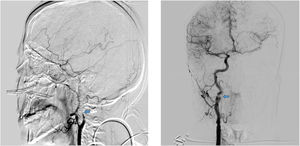

A tenor de los resultados analíticos descritos previamente, se decidió la realización de angiografía cerebral para una detección de vasculitis. Se constató: en el eje derecho una placa de ateroma en el origen de la ACI, además de una imagen de seudoaneurisma de 6,5 x 7 mm con un cuello de 3 mm, con una lobulación en su cara posterior, sugestiva de disección crónica, con adecuada permeabilidad distal. En eje carotídeo izquierdo, se visualiza oclusión de la ACI posbulbar con afilamiento del calibre y posterior oclusión (signo de la llama) sugestiva de disección aguda con adecuada colateralidad (fig. 3).

Imágenes de arteriografía por sustracción digital en las que se observa en la imagen de la izquierda una oclusión de la ACI izquierda posbulbar con afilamiento del calibre y posterior oclusión (signo de la llama) sugestiva de disección aguda. En la imagen de la derecha, se constata ateromatosis carotídea con una imagen de seudoaneurisma sugestivo de disección crónica.